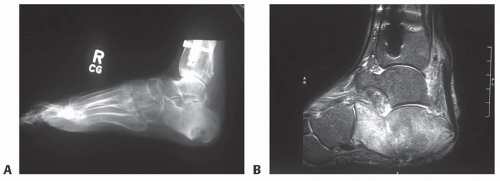

Three-view plain radiographs of the foot and ankle are the first test to order, and will help give clear definition of bony anatomy, presence of hardware or radiopaque foreign bodies, and can detect subtle changes of osteomyelitis as early as 10 to 14 days but typically requires 3 weeks of active infection before changes will be found.3

MRI is the most sensitive and specific modality for diagnosis of osteomyelitis, as early as 3 to 5 days (FIG 1B).6,7